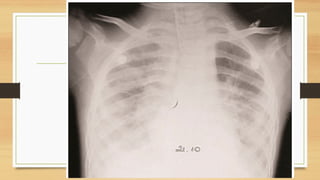

Avaliação da radiografia de tórax

Sequência para avaliação

A: Airways (traqueia, brônquios, pulmões e

pleura)

B: Bones (costelas, clavículas e coluna)

C: Circulation ( coração, vasos e mediastino)

D: Diafragma

E: Exterior (tubos, cateteres e sondas)

• Radiograficamente observa-se infiltrado alveolar difuso,

incaracterístico e muitas vezes compatível com edema pulmonar de

origem cardiogênica. Pode haver derrame pleural.

DIAGNÓSTICO

• Critérios de Berlim:

• Tempo: dentro de uma semana de um insulto clínico;

• Imagem de tórax (Rx ou TC): opacidades bilaterais não explicadas por derrames, colapso

lobar/pulmonar ou nódulos;

• Origem do edema: IR não completamente explicada por insuficiência cardíaca ou sobrecarga

de fluidos;

• Hipoxemia: PaO2/ FiO2 ≤ 300; Leve: entre 200 e 300; Moderada:

entre 100 e 200; Grave: menor que 100.

• 2.

Avaliação da radiografiade tórax Sequência para avaliação A: Airways (traqueia, brônquios, pulmões e pleura) B: Bones (costelas, clavículas e coluna) C: Circulation ( coração, vasos e mediastino) D: Diafragma E: Exterior (tubos, cateteres e sondas)

DIAGNÓSTICO • Critérios deBerlim: • Tempo: dentro de uma semana de um insulto clínico; • Imagem de tórax (Rx ou TC): opacidades bilaterais não explicadas por derrames, colapso lobar/pulmonar ou nódulos; • Origem do edema: IR não completamente explicada por insuficiência cardíaca ou sobrecarga de fluidos; • Hipoxemia: PaO2/ FiO2 ≤ 300; Leve: entre 200 e 300; Moderada: entre 100 e 200; Grave: menor que 100.